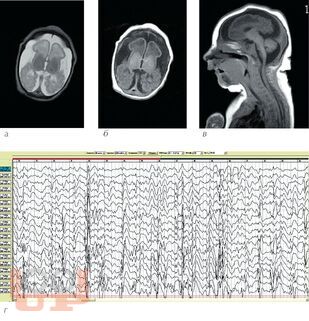

В учебном пособии рассматривается проблема диагностики и лечения резистентных форм эпилепсии у детей. Анализ материала основан на собственном опыте работы и данных литературы. В пособие включены редкие формы резистентных эпилептических энцефалопатий у детей. Особое внимание уделено нейрохирургическим методам лечения.